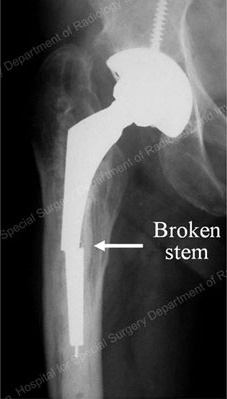

Mechanical wear and tear leading to loosening of the prosthesis (implant) is one of the most frequent forms of mechanical failure. However, other forms of mechanical failure are possible, like breakage of the prosthesis, such as may occur during a trauma like a fall or auto collision (Figure 4).

Figure 4: X-ray detailing the broken stem section of a total hip replacement prosthesis